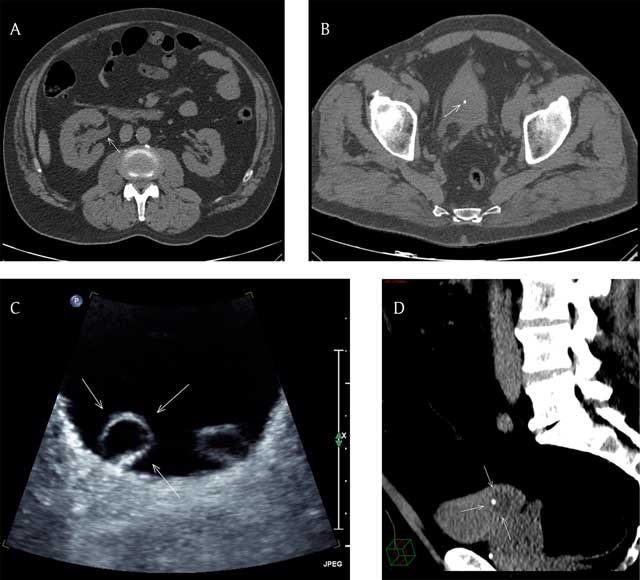

CT scan showed a right uretero-pyelo-calyceal dilatation (Figure 1A, arrow) with the presence of a 3.6 mm hyperdense stone in an almost empty bladder (Figure 1B, arrow). A non-obstructive left renal stone was also present. The rest of the exam was unremarkable. The patient was discharged home after he received the post-hospital discharge protocol specific to his case.

(A) Axial CT scan image (non-contrast) at the level of the abdomen showing right uretero-pyelo-calyceal dilatation (arrow). (B) Axial CT scan image (non-contrast) at the level of the pelvis showing a 3.6 mm hyperdense stone in an almost empty bladder (arrow). (C) Axial US image of the bladder showing bilateral ureterocele, more prominent at right (arrows). (D) Reformatted sagittal CT scan (non-contrast) image with narrow window width of the pelvis showing the urine filled right ureterocele with the stone located inside (arrows).

Three weeks later, as part of the regular follow-up, an abdominal ultrasound (US) was performed that showed resolution of the right hydronephrosis with evidence of bilateral ureterocele [1], more prominent at right (Figure 1C, arrows). No urinary tract stone was seen.

Retrospectively, a review of the multiplanar reformatted CT scan images with narrow window width showed a subtle density difference between the empty bladder and the urine-filled right ureterocele with the stone located actually in the ureterocele (Figure 1D, arrows) and not freely in the bladder.